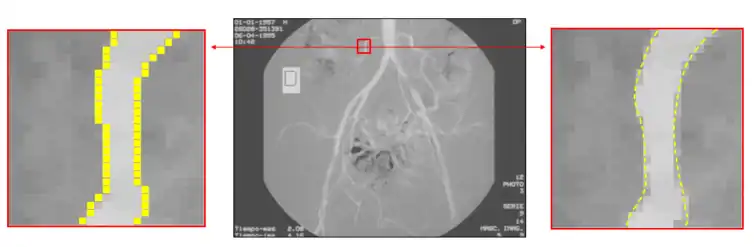

Subpixel

To increase the precision of edge detection, several subpixel techniques had been proposed, including curve-fitting, moment-based,[22][23] reconstructive, and partial area effect methods.[24] These methods have different characteristics. Curve fitting methods are computationally simple but are easily affected by noise. Moment-based methods use an integral-based approach to reduce the effect of noise, but may require more computations in some cases. Reconstructive methods use horizontal gradients or vertical gradients to build a curve and find the peak of the curve as the sub-pixel edge. Partial area effect methods are based on the hypothesis that each pixel value depends on the area at both sides of the edge inside that pixel, producing accurate individual estimation for every edge pixel. Certain variants of the moment-based technique have been shown to be the most accurate for isolated edges.[23]